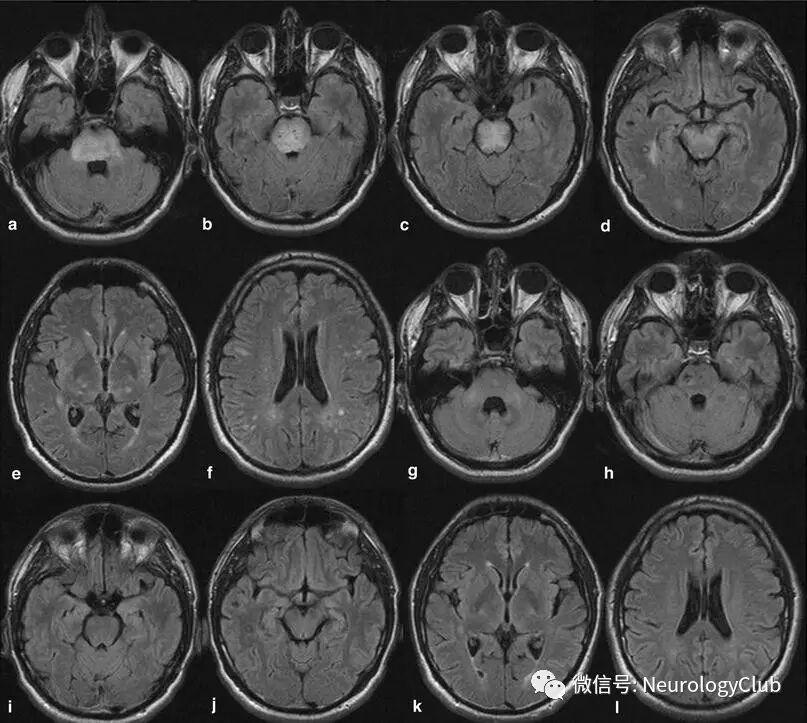

影像学表现可分为四型:顶枕型,全脑分水岭型,额上回型和中央变异型。影像学分型和水肿严重程度都不与临床表现分型和严重程度相关。额叶和颞叶受累者约占75%。累及基底节和脑干者有1/3,累及小脑者约占半数。这些部位的水肿一般是伴随着顶枕部位的受累。病变不累及顶枕区域者少见。仅累及单侧大脑和孤立性脑干与小脑水肿者需要排除其它疾病。

(图3:均为黑水像;A-C:顶枕型PRES;D-F:全脑分水岭型PRES;G-I:额上回型PRES)

(图4:均为黑水像;中央变异型PRES